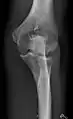

- Knee - AP and Lateral. Intra Condular projections on request

Right knee, anteroposterior

Right knee, lateral

Patella, (slightly skew) skyline